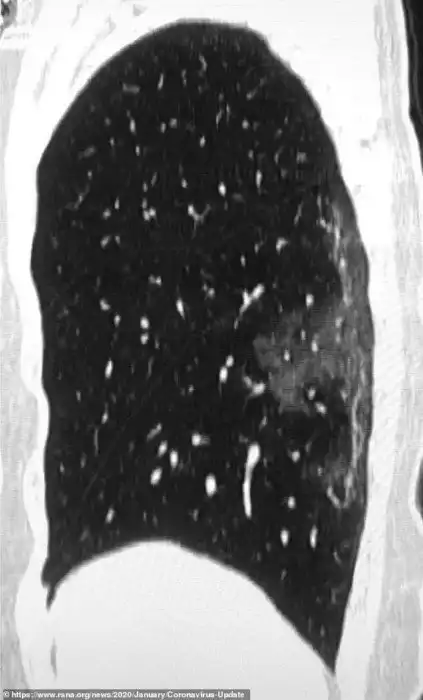

Умерший 44-летний мужчина из Китая жил в Ухани и работал на местном рынке морепродуктов, который, вероятно, стал источником нового вируса. Он был госпитализирован 25 декабря 2019 года после двух недель болезни. Врачи диагностировали у него пневмонию и острый респираторный дистресс синдром. Несмотря на лечение, он умер неделю спустя. Субплевральные уплотнения видны в его легких очень отчетливо. На снимках видно, как легкие со временем, от снимка А до снимка F, все сильнее заполняются жидкостью. Компьютерная томограмма легких 54-летней женщины, подхватившей коронавирус во время поездки в Ухань, показывает схожую картину.

Это - снимки 54-летней женщины, у которой по возвращении из Ухани была диагностировала сильная вирусная пневмония. В ходе лечения врачи давали ей кислород и антибиотики.